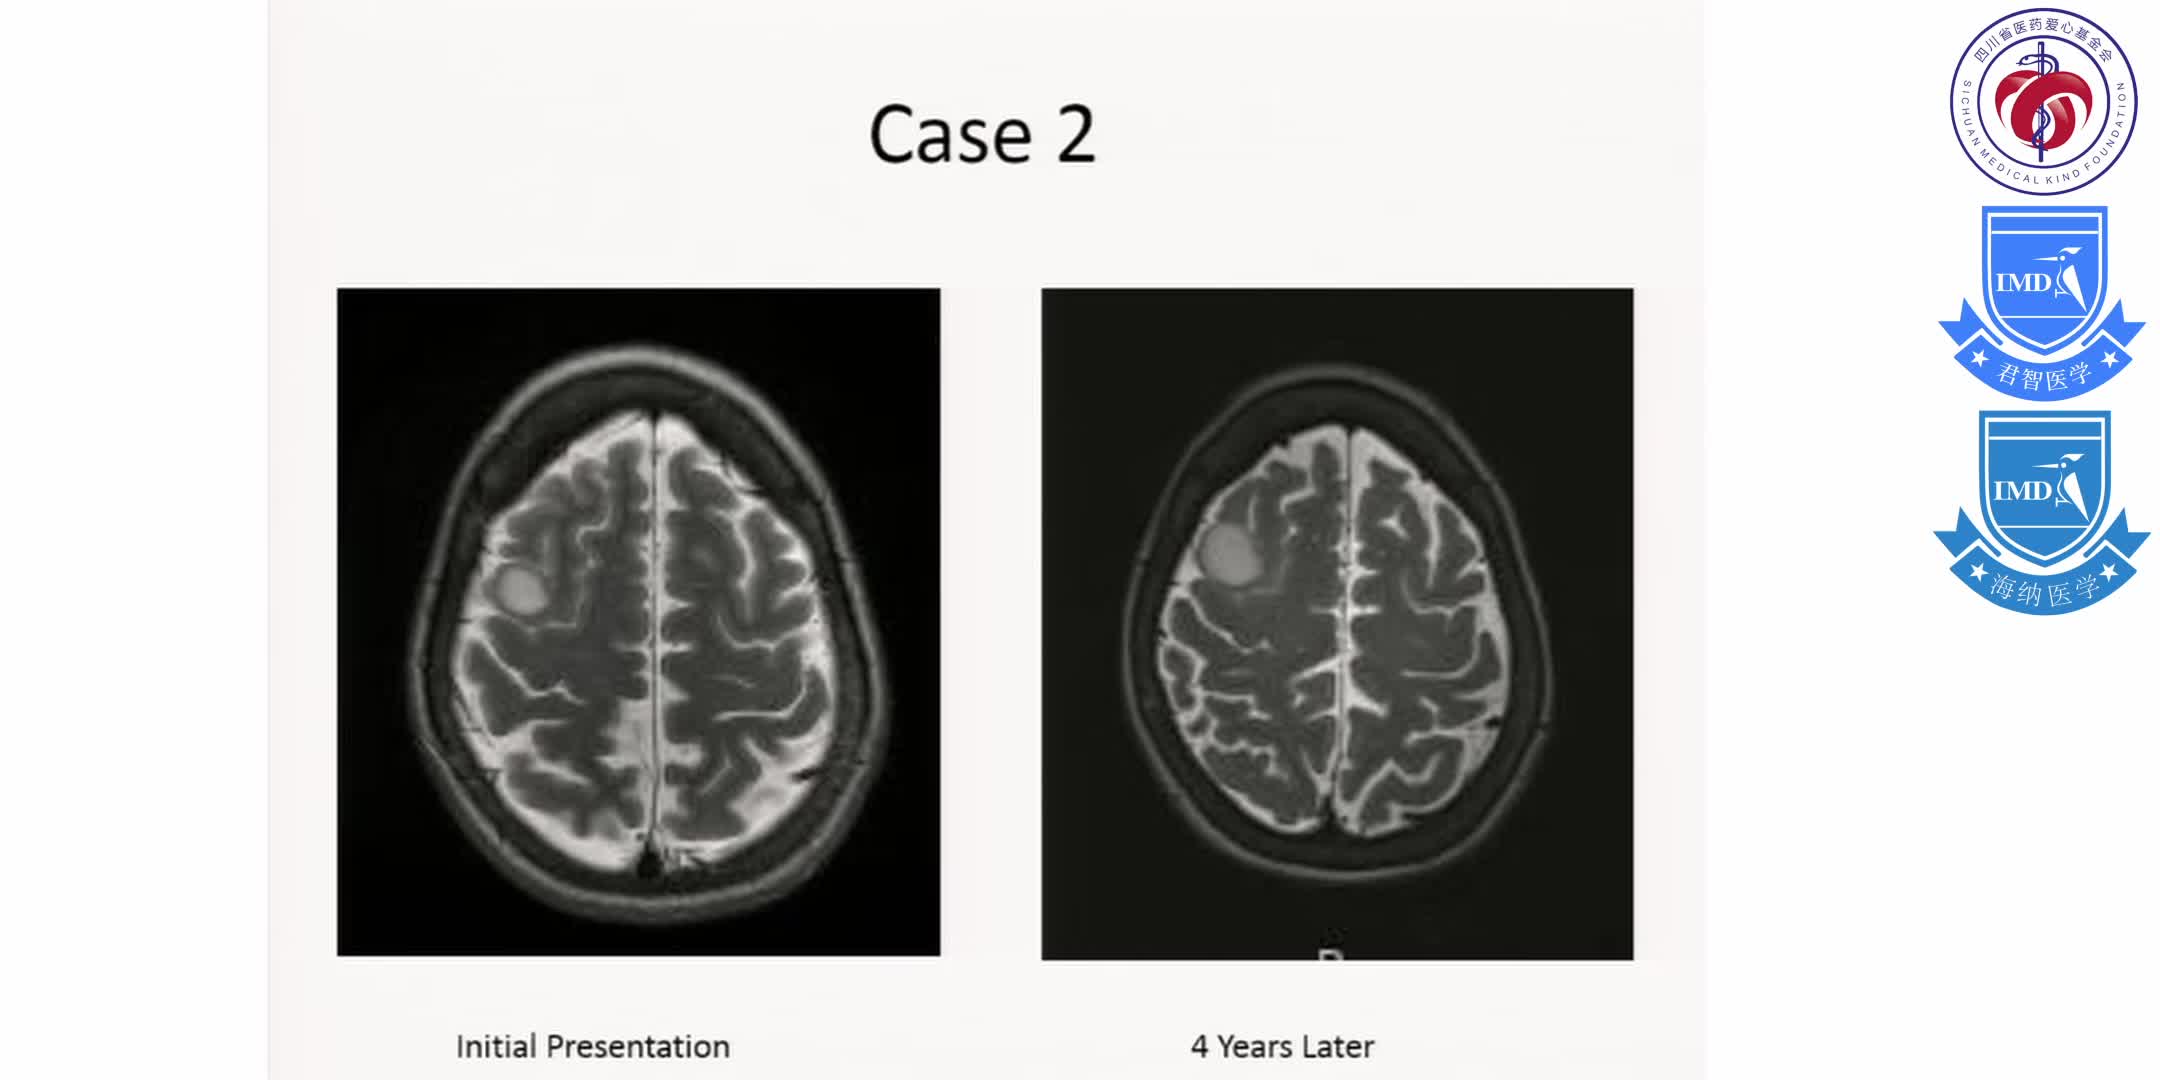

Initial Treatment, Including Scenarios Requiring Urgent and Multi-disciplinary Management for Primary Brain Tumors 3 医学讲坛 2025年05月08日 48 点赞 0 评论 454 浏览

Initial Treatment, Including Scenarios Requiring Urgent and Multi-disciplinary Management for Primary Brain Tumors 2 医学讲坛 2025年05月08日 42 点赞 0 评论 595 浏览

Initial Treatment, Including Scenarios Requiring Urgent and Multi-disciplinary Management for Primary Brain Tumors 1 医学讲坛 2025年05月08日 17 点赞 0 评论 134 浏览